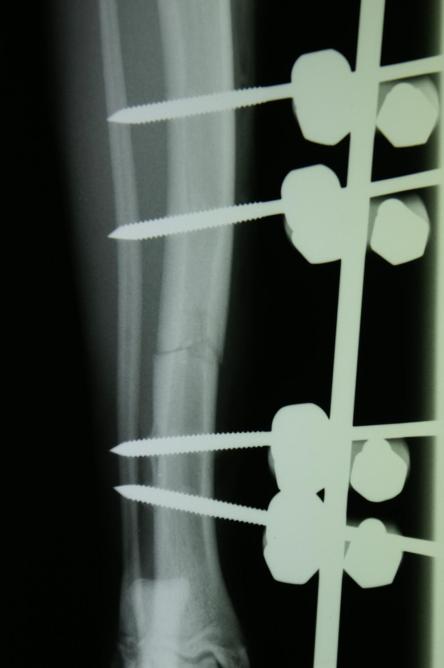

Auf dem Röntgenbild des Beines ist erkennbar, dass das Schienbein in der Mitte quer gebrochen ist. Feine Haarrisse ziehen von der Frakturspalte kniewärts. Das Wadenbein ist intakt, was die relative Stabilität des Bruchs erklärt.

Die Fraktur ist auf Dauer konservativ nicht ausreichend stabilisierbar. Hierzu müsste das Gelenk ober- und unterhalb des Bruchs (d.h. Knie- und Sprunggelenk) immobilisiert werden, was aufgrund der Anatomie eines Katzenbeines nicht möglich ist. Zusammen mit den Besitzern wird entschieden, den Bruch mit einem sogenannten Fixateur Externe zu versorgen.

Nach vier Tagen wird nochmals ein Röntgen des Brustkorbs angefertigt, auf welchem erkennbar ist, dass sowohl Lungenblutung als auch Pneumothorax verheilt sind und eine Narkose somit möglich ist. Je zwei Stahlstifte werden ober- und unterhalb der Bruchstelle durch die Haut in den Knochen gebohrt und ausserhalb des Körpers mittels Klampen, Muttern und einem Verbindungsstift verbunden, was zusammen mit der stabilisierenden Wirkung des Wadenbeins eine ausgezeichnete Fixation ergibt. Der ausserhalb der Haut liegende Teil dieser Konstruktion wird mit einem gepolsterten „Verband“ umgeben, damit die Katze mit den Metallteilen nicht an Gegenständen hängen bleibt.

„Pfüdi“ belastet nach der Operation das Bein sofort wieder sehr gut, muss aber zur besseren Heilung 6 Wochen in seiner Bewegung eingeschränkt werden. Nach dieser Zeit wird ein Röntgenbild angefertigt, welches zeigt, dass die Fraktur sehr gut verheilt ist. Der Fixateur Externe wird in einer kurzen Narkose entfernt.